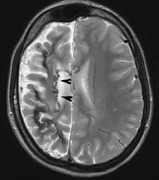

4. Cognitive impairment. Thirty percent to 60% of children with NF1 have learning difficulties, which are typically mild and nonprogressive. These include visual-spatial problem-solving difficulty, language disorders, and attention deficit disorder. The reason for this is not clear but may be related to unidentified bright objects (UBOs) seen on T2-weighted brain magnetic resonance imaging (MRI) scans. These hyperintensities are common in young patients with NF1 but decrease with advancing age. The histopathologic correlate of UBOs is unclear. It has been postulated that the prevalence of learning difficulties in children with NF1 may be related to heterozygosity of the NF1 gene (i.e., the gene may have additional functions that affect cognition when the full complement of its gene product is not expressed in the central nervous system).25,32–34

2. Subependymal nodules (SEN) are typically found along the lateral borders of the ventricles and parehncymal brain lesion (“cortical tubers”) (Figs. 14 and 15). Calcification in the first year of life is rare.132

Fig. 14. Tuberous Sclerosis Complex: Sub-Ependymal nodules. These are typically found along the lateral borders of the ventricles.132

Fig. 15. Tuberous Sclerosis Complex. (a) Patient 1: Axial CT scans demonstrating typical calcification of subependymal nodules in a 13-year-old girl with a history of seizures. (b and c) Patient 2. (b) Axial T2-weighted images demonstrate calcified subependymal nodules (arrowheads) and cortical tubers typical of tuberous sclerosis. (c) Widespread cortical tubers are seen on a coronal FLAIR sequence as thickening of the cortex and high signal of the subcortical white matter.